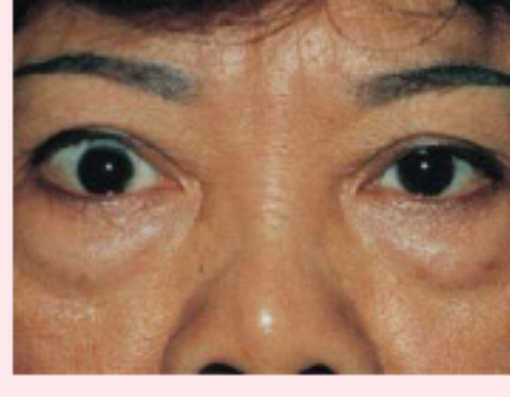

exophthalmos

protruding eyeballs and retracted eyelids